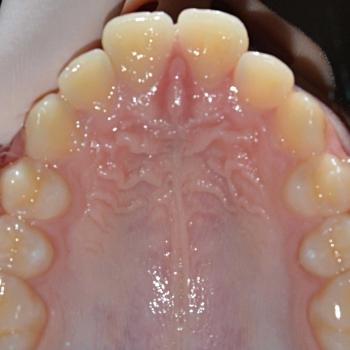

Ákos és édesanyja talán az egyik legjobb korban, 11 évesen kerestek fel a felső fogív túlzott előredőlése miatt. Az első vizsgálat alkalmával, az említett problémán túl, asszimetrikus Angle II-es harapási eltérést diagnosztizáltunk (a bal oldalon 3mm-es, a jobb oldalon 6mm-es eltéréssel)

A kezelési terv nyaki húzású headgear-t, alsó és felső hagyományos fém fogszabályozót, illetve különböző intermaxilláris gumihúzásokat tartalmazott, melyeket Ákos nagy kitartással és utasításszerűen hordott.

Ennek eredményeként sikerült a felső metszőfogakat kellőképpen visszadönteni, illetve korrigálni a harapási eltérést is, ezáltal egy esztétikailag és funkcionálisan is szép eredményt elérni.

A kezelés teljes időtartama: 2.5 év